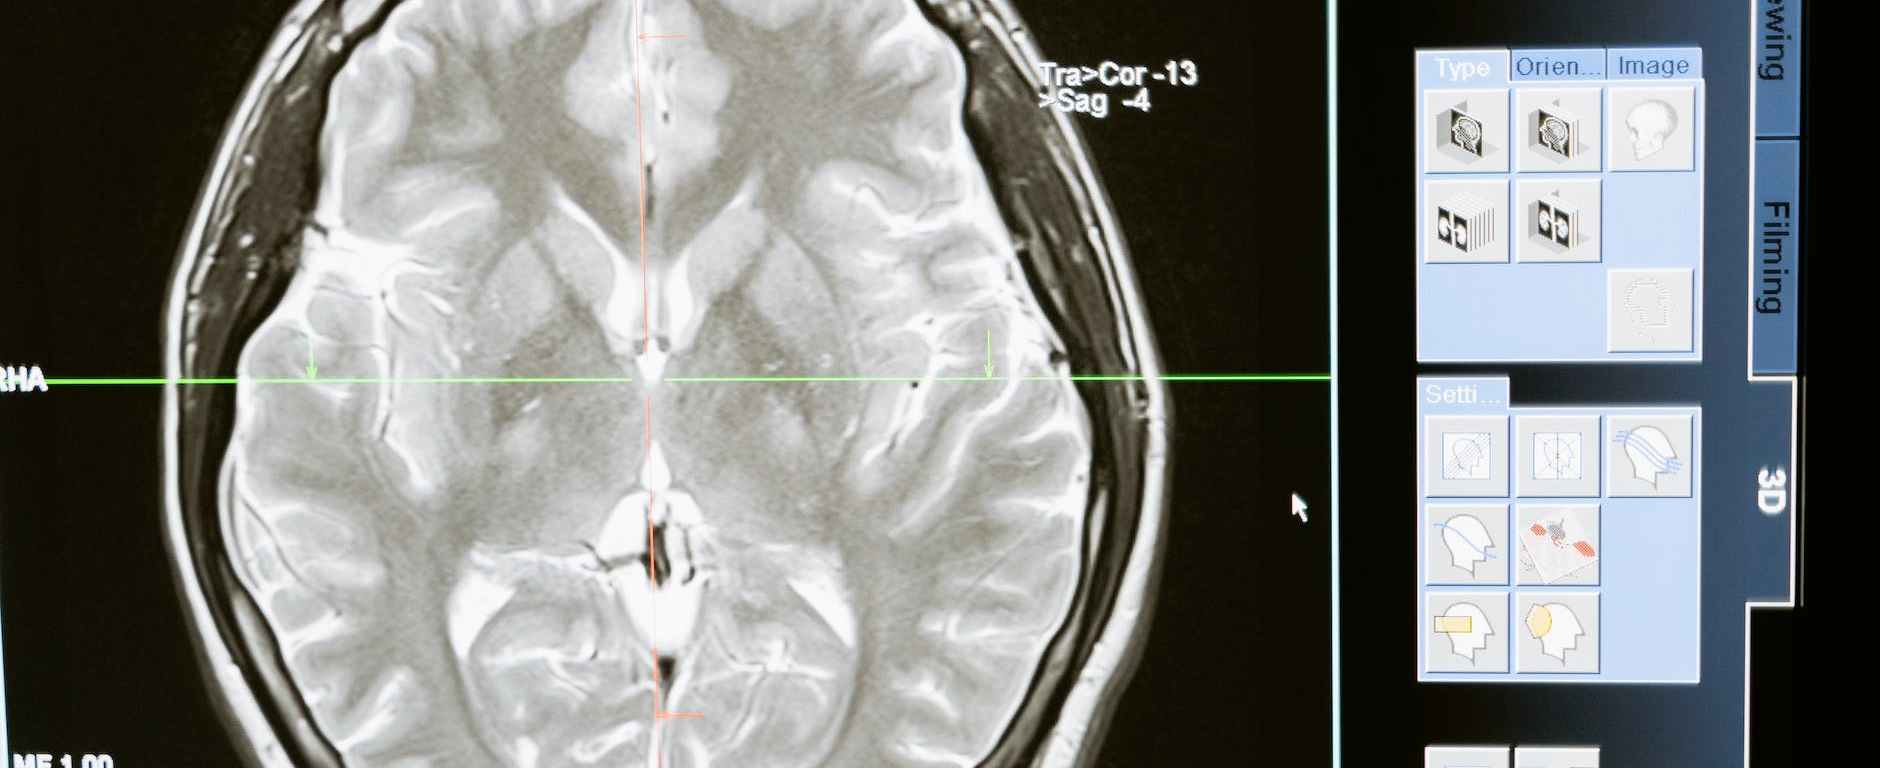

La intervención temprana ante la aparición de un ictus es de vital importancia para garantizar la mejor recuperación posible del paciente. Y es que, un ictus puede tener consecuencias devastadoras si no se trata rápidamente. Es por eso que el personal del pabellón ha recibido una formación especializada para actuar de manera eficiente y efectiva en estos casos, aprendiendo a reconocer los síntomas iniciales y a tomar medidas inmediatas para minimizar el daño cerebral.